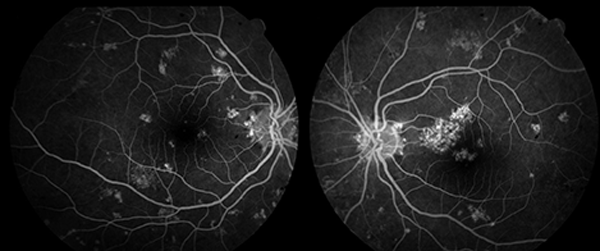

Se realizó una retinofluoresceinografía que no mostró extravasación de líquido, isquemia, ni alteraciones vasculares en tiempos tempranos ni tardíos. Se pudieron observar imágenes de hiperreflectividad debido a alteraciones del EPR (efecto ventana) (fig. 3). El electrorretinograma presentó respuesta evocada retinal de morfología y latencias adecuadas dentro de límites fisiológicos.

Figura 2. RFG ojos izquierdo y derecho.